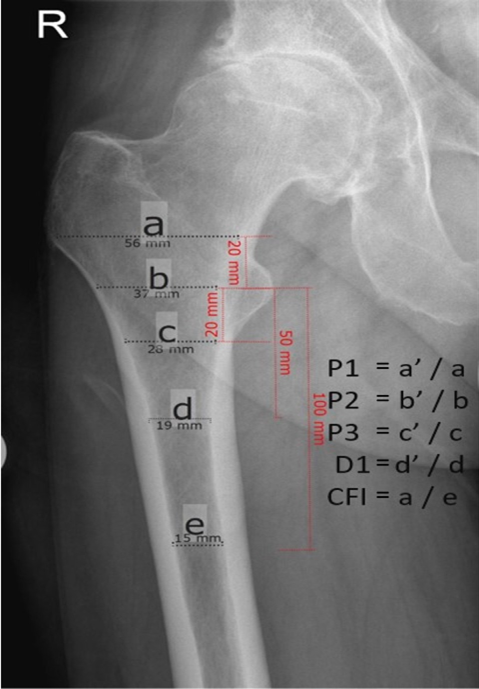

Hip stem migration (subsidence) was evaluated on anteriorposterior radiographs of the pelvic in a standing position with a film-focus-distance of 115 cm performed 5 days, 3 months and two years postoperative. The validated software “FXA” of the independent imaging core lab (RAYLYTIC, Leipzig, Germany) was used [26-28]. The software matches two images (24 months and 3 months vs. 5 days postop) using a normalized 2D grayscale cross-correlation algorithm in an iterative process using the evolutionary optimization algorithm CMA-ES [29]. Moreover, the radiographs were analyzed for radiolucent lines around the stem. The radiographs were analyzed retrospectively. The following parameters were measured on the postoperative radiographs (Figure 2,3): The Canal Flare Index (CFI), the Canal Fill Ratio (CFR), the Stem Angulation (SA) and calculated as potential influencing factors for subsidence as well as the clinical parameters: gender, weight, BMI, age and stem size.

Figure 2a: Description of the different measurements for calculating the Canal Fill Index (CFI) and Canal Fill Ratio (CFR). Fig 2a: preoperative x-ray, Fig 2b: postoperative x-ray. Canal Flare Index (CFI = a/e), Canal-Calcar Ratio (CCR = e/b); Canal Fill Ratios (CFR P1) at 2 cm above the lesser trochanter (P1 = a’/a), CFR P2 at the lesser trochanter (P2 = b’/b), CFR P3 at 2 cm below the lesser trochanter (P3 = c’/c), CFR D1 at 5 cm below the lesser trochanter (D1 = d’/d).